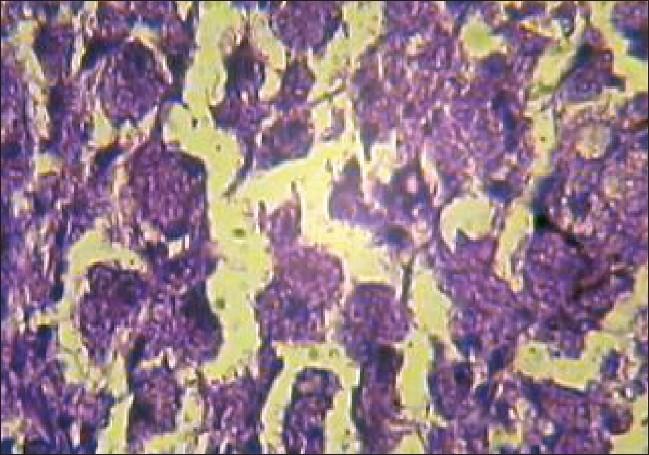

Xanthomas are often a manifestation of underlying lipid abnormalities. A 50-year-old male presented to our hospital with the lesions of multiple tuberous xanthomas all over the body. Routine investigations and systemic examination were normal. Lipid profile was within normal range and serum protein electrophoresis showed normal pattern. Histopathology from a nodular lesion showed collection of foamy macrophages in the dermis. We present a case of normolipemic tuberous xanthomas, which is an uncommon occurrence.

黄瘤通常是潜在脂质异常的一种表现。一名50岁男性因全身多处结节性黄瘤病变前来我院就诊。常规检查和全身检查均正常。血脂谱在正常范围内,血清蛋白电泳显示正常模式。结节性病变的组织病理学检查显示真皮内有泡沫状巨噬细胞聚集。我们报告一例血脂正常的结节性黄瘤病例,这种情况并不常见。